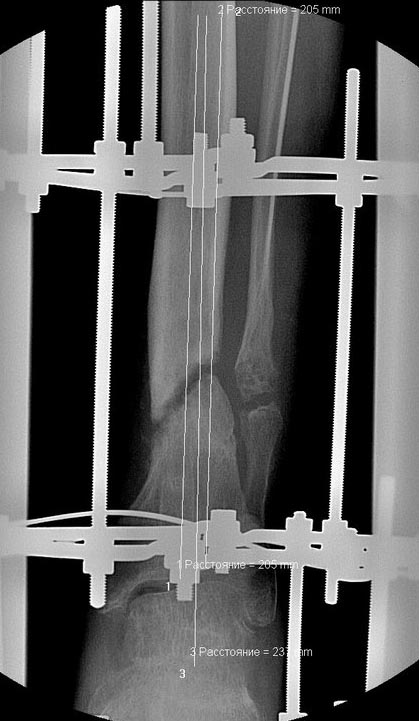

В феврале 2014 г выполнил первым этапом: Фиксацию ложного

сустава в АНФ с восстановлением осей сегментов. Через семь дней БИОС с

рассверливанием.

После операции - вальгус голеностопного сустава. Гладкое течение

послеоперационного периода. Нагрузка по переносимости боли. Через 6

недель динамизация, через 2 недели стали мигрировать 2 фронтальных

винта. Пытался подкрутить, пришлось удалить.

Через 6 мес. контроль - линия ложного сустава прослеживается, но имеется

периостальная костная мозоль.

Не хватает стабильности.